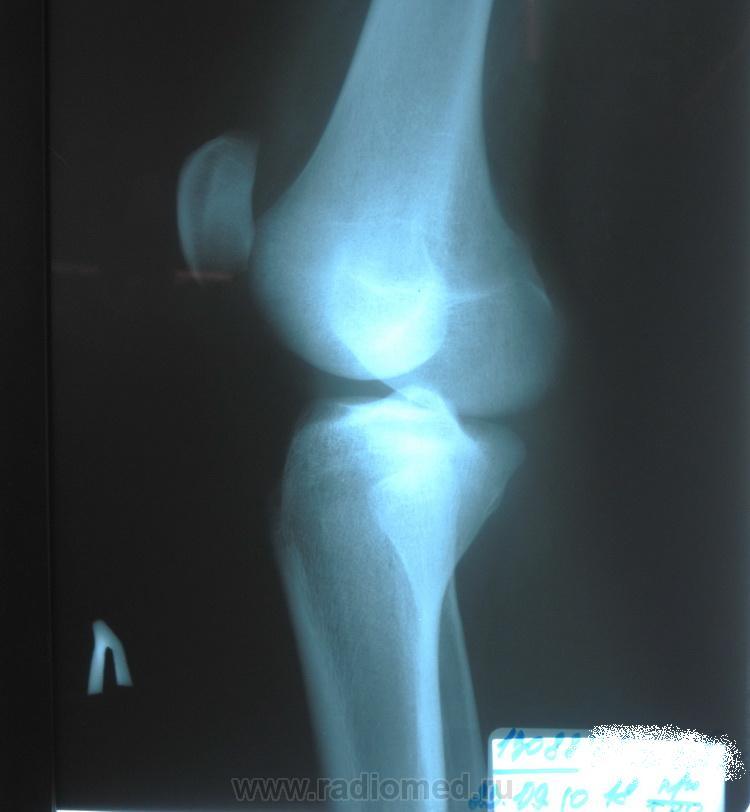

Заболевания и медицинские снимки: Жидкость в коленной чашечке

Раздел: Галерея прозрений